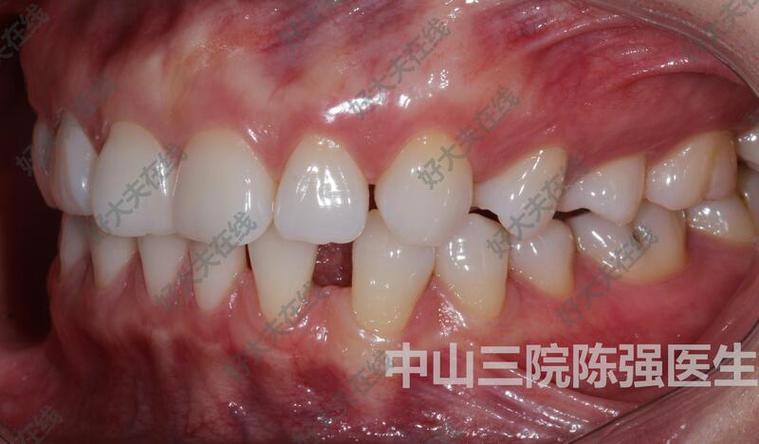

(图片来源网络,侵删)- 牙根形态与位置: 两颗需要移动的牙齿(通常是前牙或后牙)的牙根长度、粗细、弯曲度、根分叉情况可能不同,牙根较长、较粗或弯曲度大的牙齿,移动阻力通常更大,移动速度可能较慢,牙根在牙槽骨内的初始位置也可能导致受力不均。